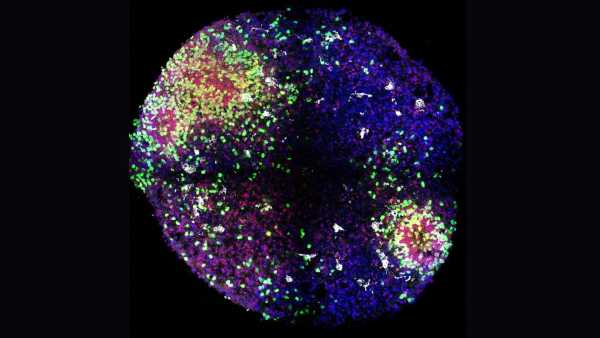

Ці менінгеальні лімфатичні судини, зображені рожевим кольором, знаходяться всередині менінгеального шару (синім) у мозку та забезпечують один із дренажних шляхів органу для рідини та відходів. (Зображення: Дженніфер Мансон)